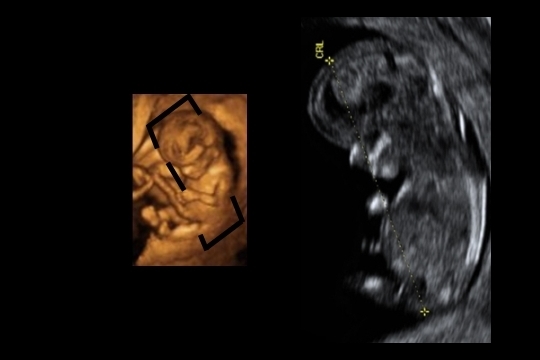

Corte sagital